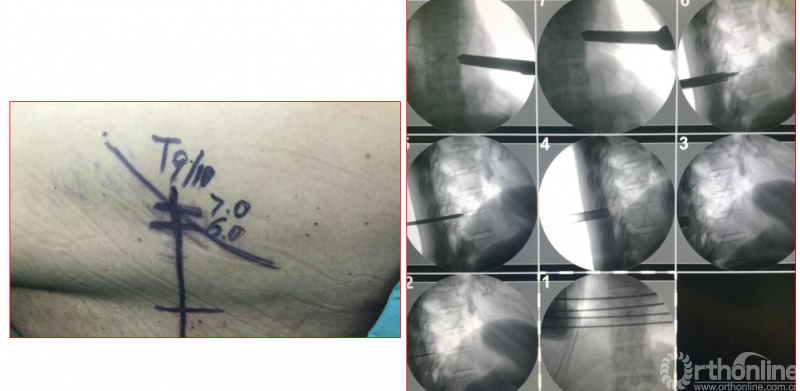

手术资料

术中资料